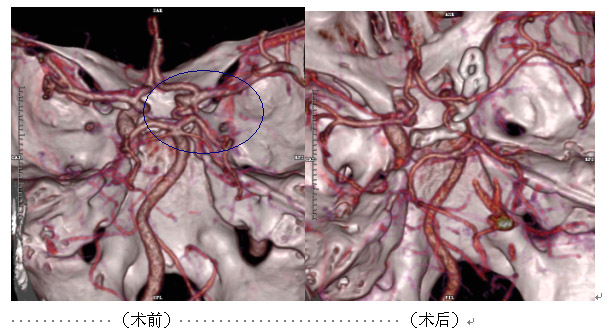

這名患者中年男性,3天前出現(xiàn)劇烈頭痛�,外院頭顱CT:大腦外側(cè)裂可疑高密度影,未能確診��。遂轉(zhuǎn)來(lái)我院���,經(jīng)全面檢查后����,明確診斷為:蛛網(wǎng)膜下腔出血�。我院神經(jīng)外科進(jìn)一步行頭顱CTA檢查示:前交通動(dòng)脈囊狀動(dòng)脈瘤���,證實(shí)其為出血“元兇” ����。后經(jīng)手術(shù)治療���,獲得康復(fù)���。